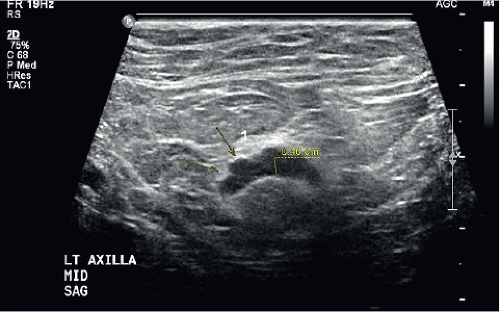

In the male breast, the majority of malignancies are subareolar and metastasis to the axilla is common. It has been reported that 50% of men have axillary nodal metastasis at initial presentation (9). US of the ipsilateral axilla should be included. It is important to note the morphology of the nodes matters more than the overall size. Displacement of the fatty hilum, increased cortical thickness >3 mm or irregular contour of the cortex are suspicious findings and warrant tissue sampling (Fig. 19-5). If US-guided axillary lymph node biopsy reveals metastatic disease, then additional staging examinations similar to what female breast cancer patients undergo are indicated. Computed tomography (CT) of the thorax and abdomen and Tc99m-HDP whole-body bone scan are recommended.